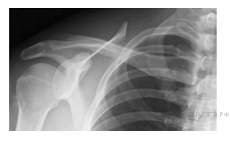

Какой сустав человека изображен на рентгеновском снимке?

Варианты ответов

- тазобедренный

- коленный

- плечевой

- локтевой